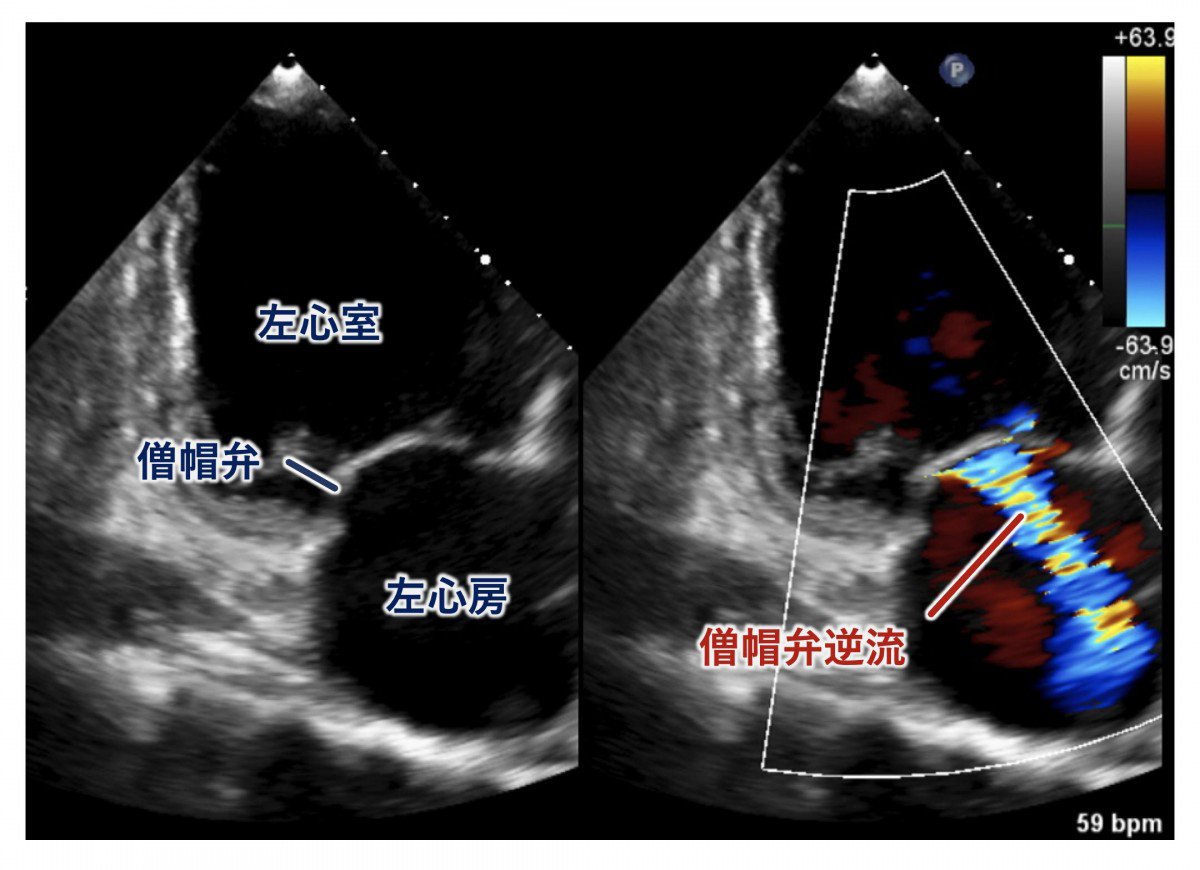

③僧帽弁逆流症 (MR) の診断

診断は心臓超音波検査(心エコー図検査)によって行われます。主に、体表面から行う経胸壁心エコー図検査で、僧帽弁の性状や逆流の重症度、心機能の評価を行います。この検査は患者さんの負担も少なく、繰り返し行うことができるため、診断や病気の進行を知ることができます。

経胸壁心エコー図による僧帽弁逆流評価